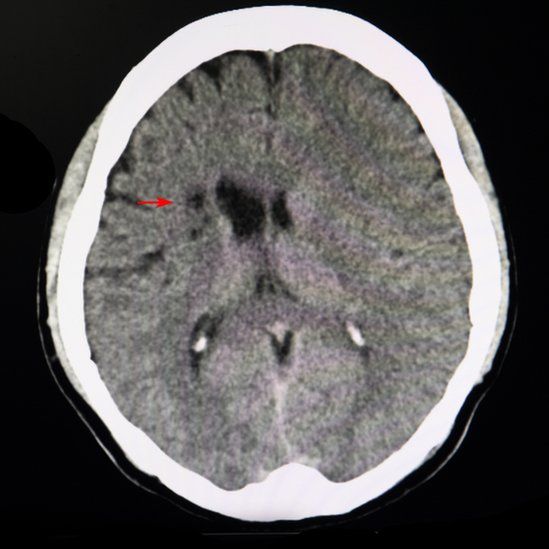

El daño es tan pequeño que no generan síntomas obvios y sólo se pueden observar con una imagen por resonancia magnética (IRM) o una tomografía computarizada (escaneo TC).

«Se ven como un pequeño puntito», indica la doctora Koppel. «Muchas veces, cuando les preguntamos, los pacientes ni se dieron cuenta de que les pasó algo».